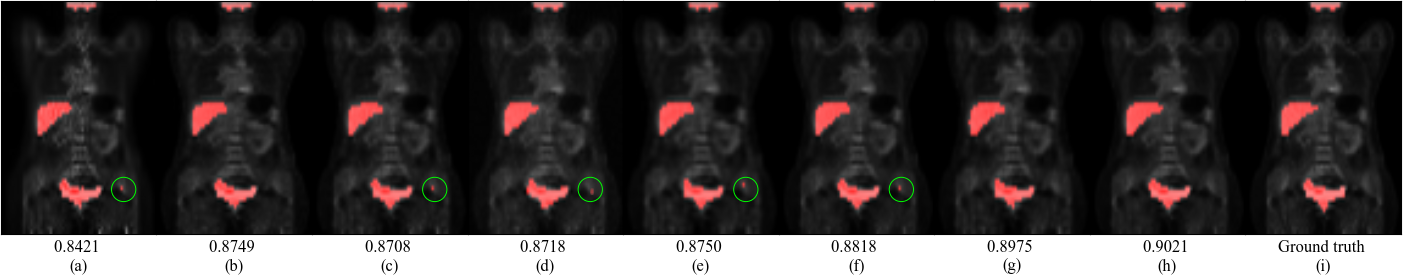

Generally, the Unet-score increases with the image quality. The Unet-score within organs of SGSGAN-3D-Unet and SGSGAN-DCITN is improved, compared with their counterparts (3D-Unet and DCITN) and other methods. Furthermore, the Unet-score-SG of SGSGAN-3D-Unet and SGSGAN-DCITN are much higher than their Unet-score, which verifies that our framework also conduces to the down-stream segmentation task. Fig. 5 shows examples of segmentation results. More apparent segmentation errors appear in BM3D, 3D-cGAN, CycleWGAN, 3D-Unet, and DCITN (marked as green circles), whereas SGSGAN-3DUnet and SGSGAN-DCITN well segment the ROIs with SG.